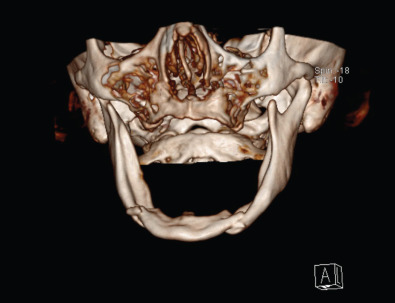

If maxillofacial trauma is suspected, radiographs will most likely be performed. Plain films of the maxillofacial region such as the mandible series, Waters view and submental vertex view are almost always now being replaced by the computed tomography (CT) scan. CT scans of the maxillofacial region give much better detail in a 3-dimensional aspect to assist the provider in diagnosing the injury and formulating a treatment plan. Occasionally, patients seen in the outpatient office will have an orthopantomogram (panorex) as a screening film for mandibular trauma. The orthopantomogram should have another radiograph in a second plane such as an AP film or CT scan to fully assess the injury. A CT scan is the optimal study to assess maxillary and upper face trauma. Additionally, the CT scan can be carried through the skull to assess bony and soft tissue injuries to the central nervous system and cervical spine ( Figs. 1.21.3–1.21.6 ).